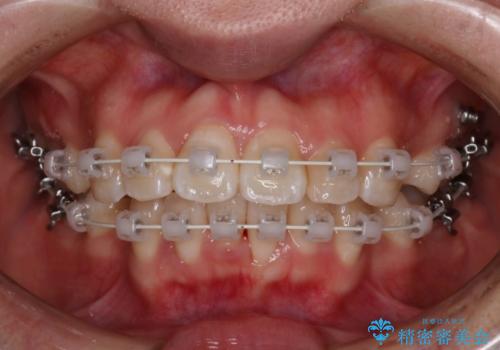

- 矯正装置

- 審美装置